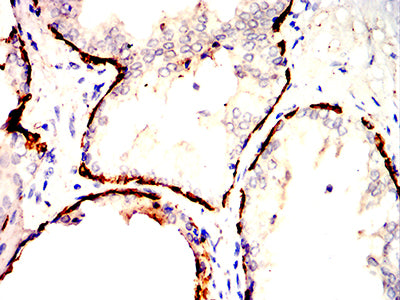

Immunohistochemical analysis of paraffin-embedded human prostatic cancer tissues using KRT14 mouse mAb with DAB staining.